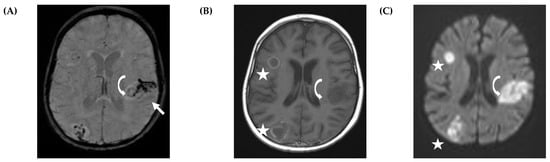

5.2. CNS Manifestations

- Nickerson, J.P.; Richner, B.; Santy, K.; Lequin, M.H.; Poretti, A.; Filippi, C.G.; Huisman, T.A. Neuroimaging of pediatric intracranial infection--part 2: TORCH, viral, fungal, and parasitic infections. J. Neuroimaging 2012, 22, e52–e63. [Google Scholar] [CrossRef] [PubMed]

- Gavito-Higuera, J.; Mullins, C.B.; Ramos-Duran, L.; Olivas Chacon, C.I.; Hakim, N.; Palacios, E. Fungal Infections of the Central Nervous System: A Pictorial Review. J. Clin. Imaging Sci. 2016, 6, 24. [Google Scholar] [CrossRef]

- Antulov, R.; Dolic, K.; Fruehwald-Pallamar, J.; Miletic, D.; Thurnher, M.M. Differentiation of pyogenic and fungal brain abscesses with susceptibility-weighted MR sequences. Neuroradiology 2014, 56, 937–945. [Google Scholar] [CrossRef]

- Mathur, M.; Johnson, C.E.; Sze, G. Fungal infections of the central nervous system. Neuroimaging Clin. N. Am. 2012, 22, 609–632. [Google Scholar] [CrossRef]